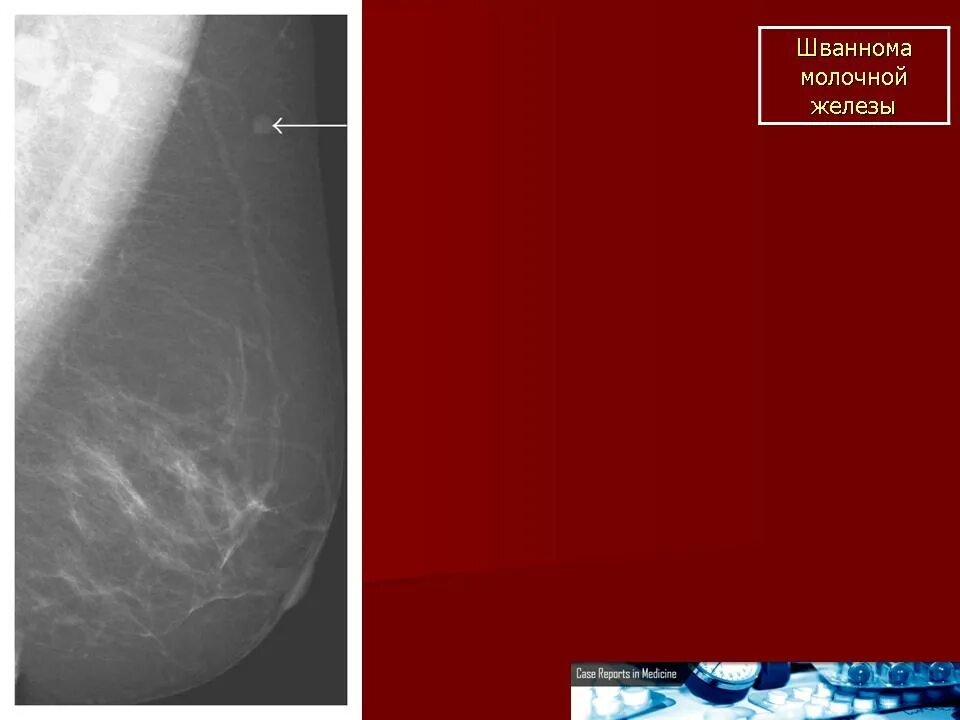

Шваннома молочной железы. лейомиома молочной железы. гамартома молочной железы. гемангиома молочной железы.